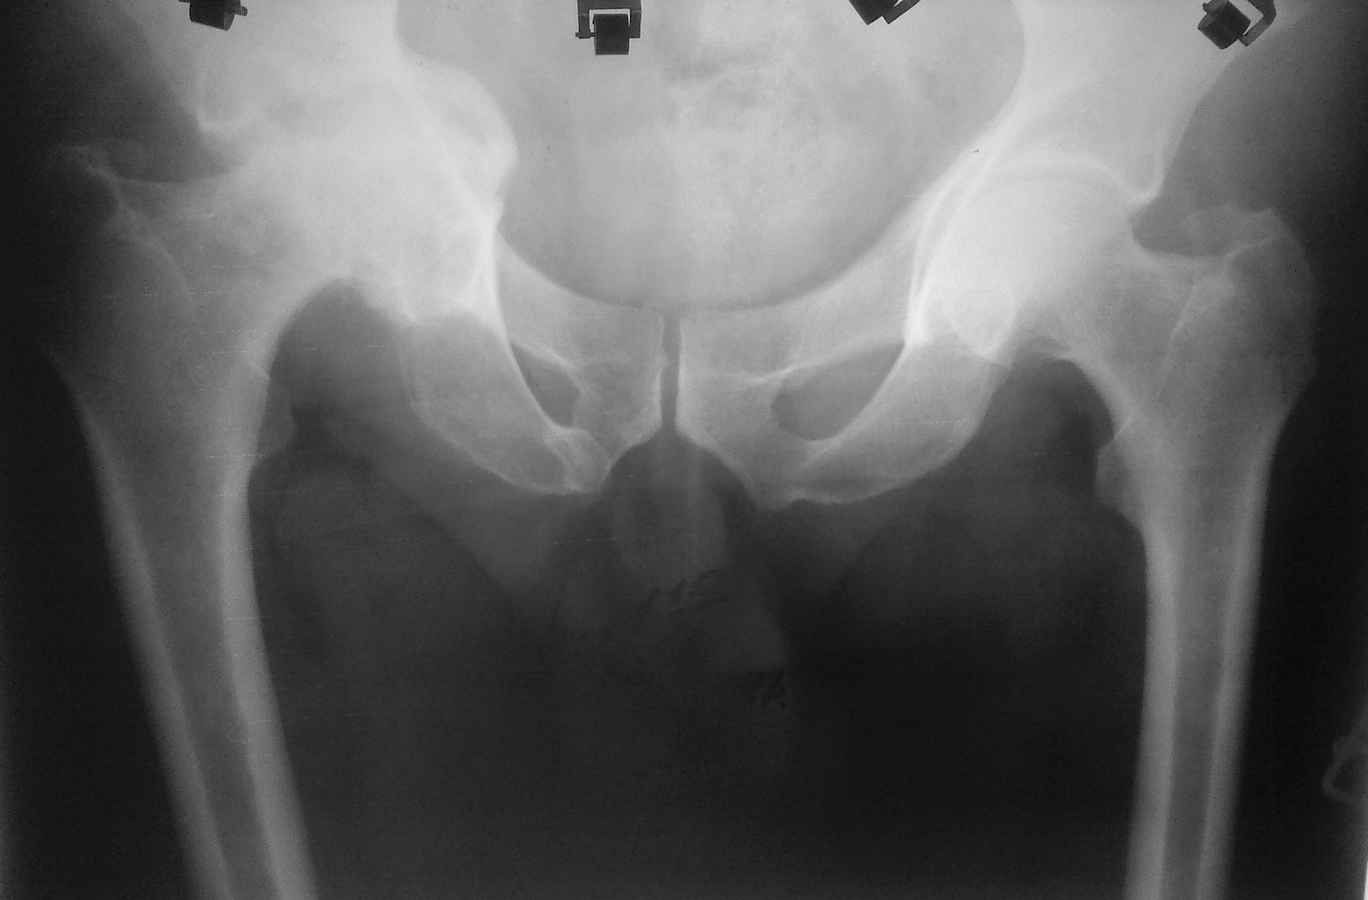

Здравствуйте. Уважаемые коллеги, поделитесь опытом у кого какая тактика при протрузионных коксартрозах

У нас в клинике принято выполнять костную пластику дна стружкой из гололки, а потом цементную чашку (снимки прилагаю). Выскажите свои взгляды на эту проблему, пожалуйста.